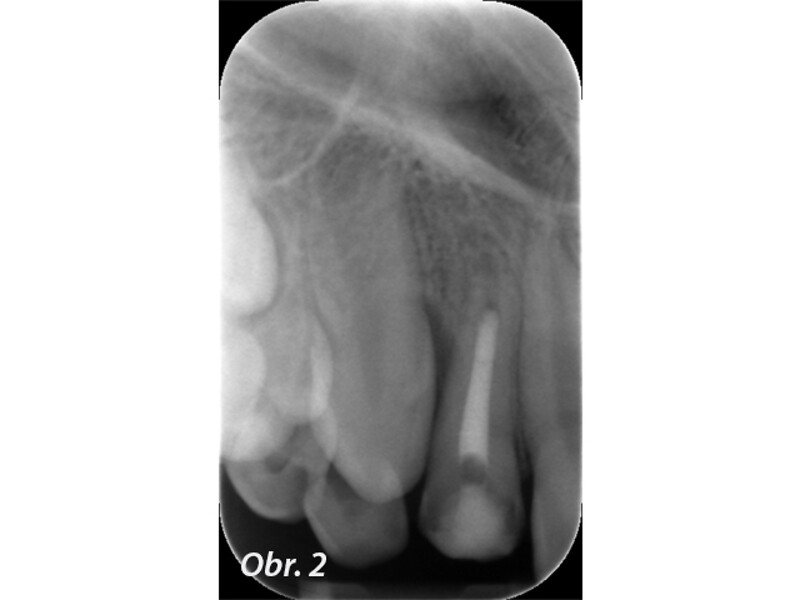

Indikační šíře MTA: Soubor kazuistik